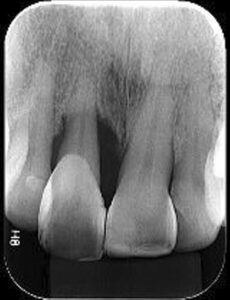

O Exame Radiográfico não evidencia Perda Óssea

O Exame Radiográfico evidencia Perda Óssea

Exame Radiográfico

O exame Radiográfico é muito importante, deve ser observado o volume e a posição da crista óssea para que se tenha uma melhor condição de previsibilidades, viabilidade e escolha da técnica a ser utilizada. (RX Periapical e Interproximal)